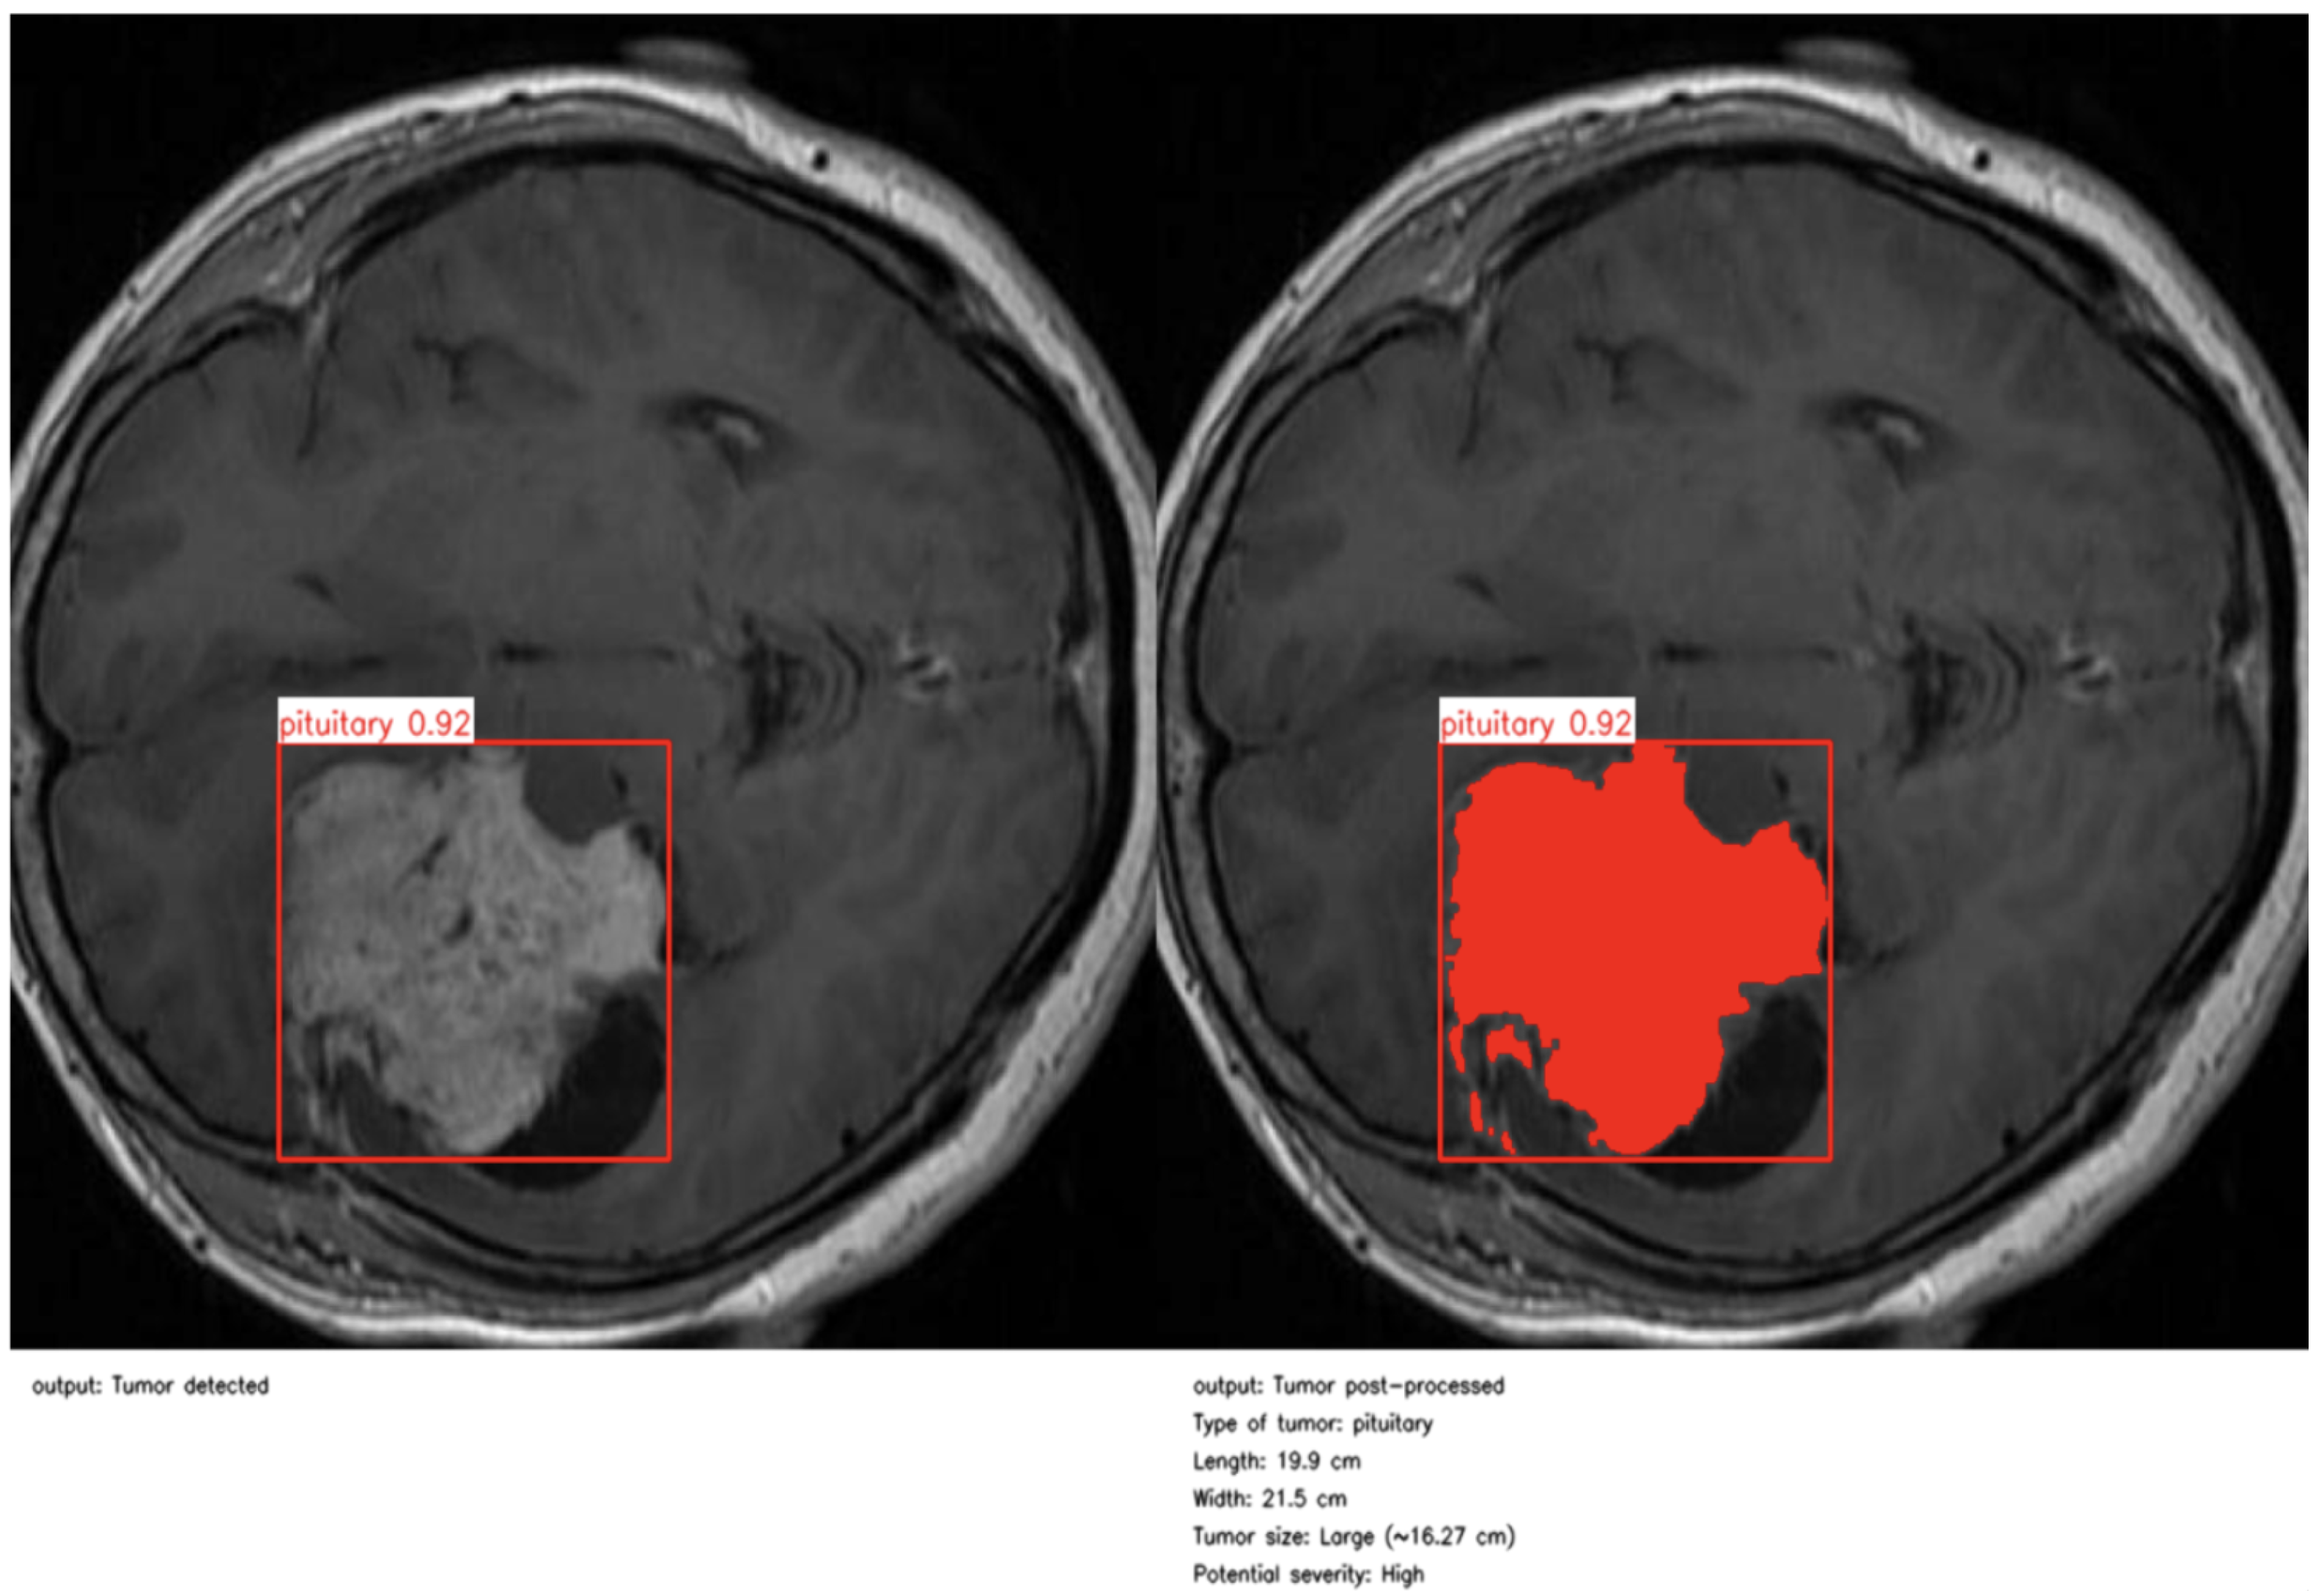

As illustrated in Figure 4 and Figure 5, the proposed method enables precise post-detection analysis. For instance, a pituitary macroadenoma, detected with a high confidence score (0.92), exhibits a computed area of 16.27 cm2, corresponding to a large and clinically significant lesion. Similarly, a glioma lesion identified with 0.93 confidence yields dimensions of 10.2 × 12.1 cm and an estimated size of 9.5 cm2, indicative of aggressive growth potential. Notably, the contrast-enhanced pipeline enables the detection of peripheral hyperintense foci—small white patches within the ROI—which may correspond to early infiltrative zones or satellite tumor loci. These critical features are often indistinguishable in raw YOLO segmentation, highlighting the added diagnostic value of our approach.

Figure 5. Second example of post-processing and clinical report.